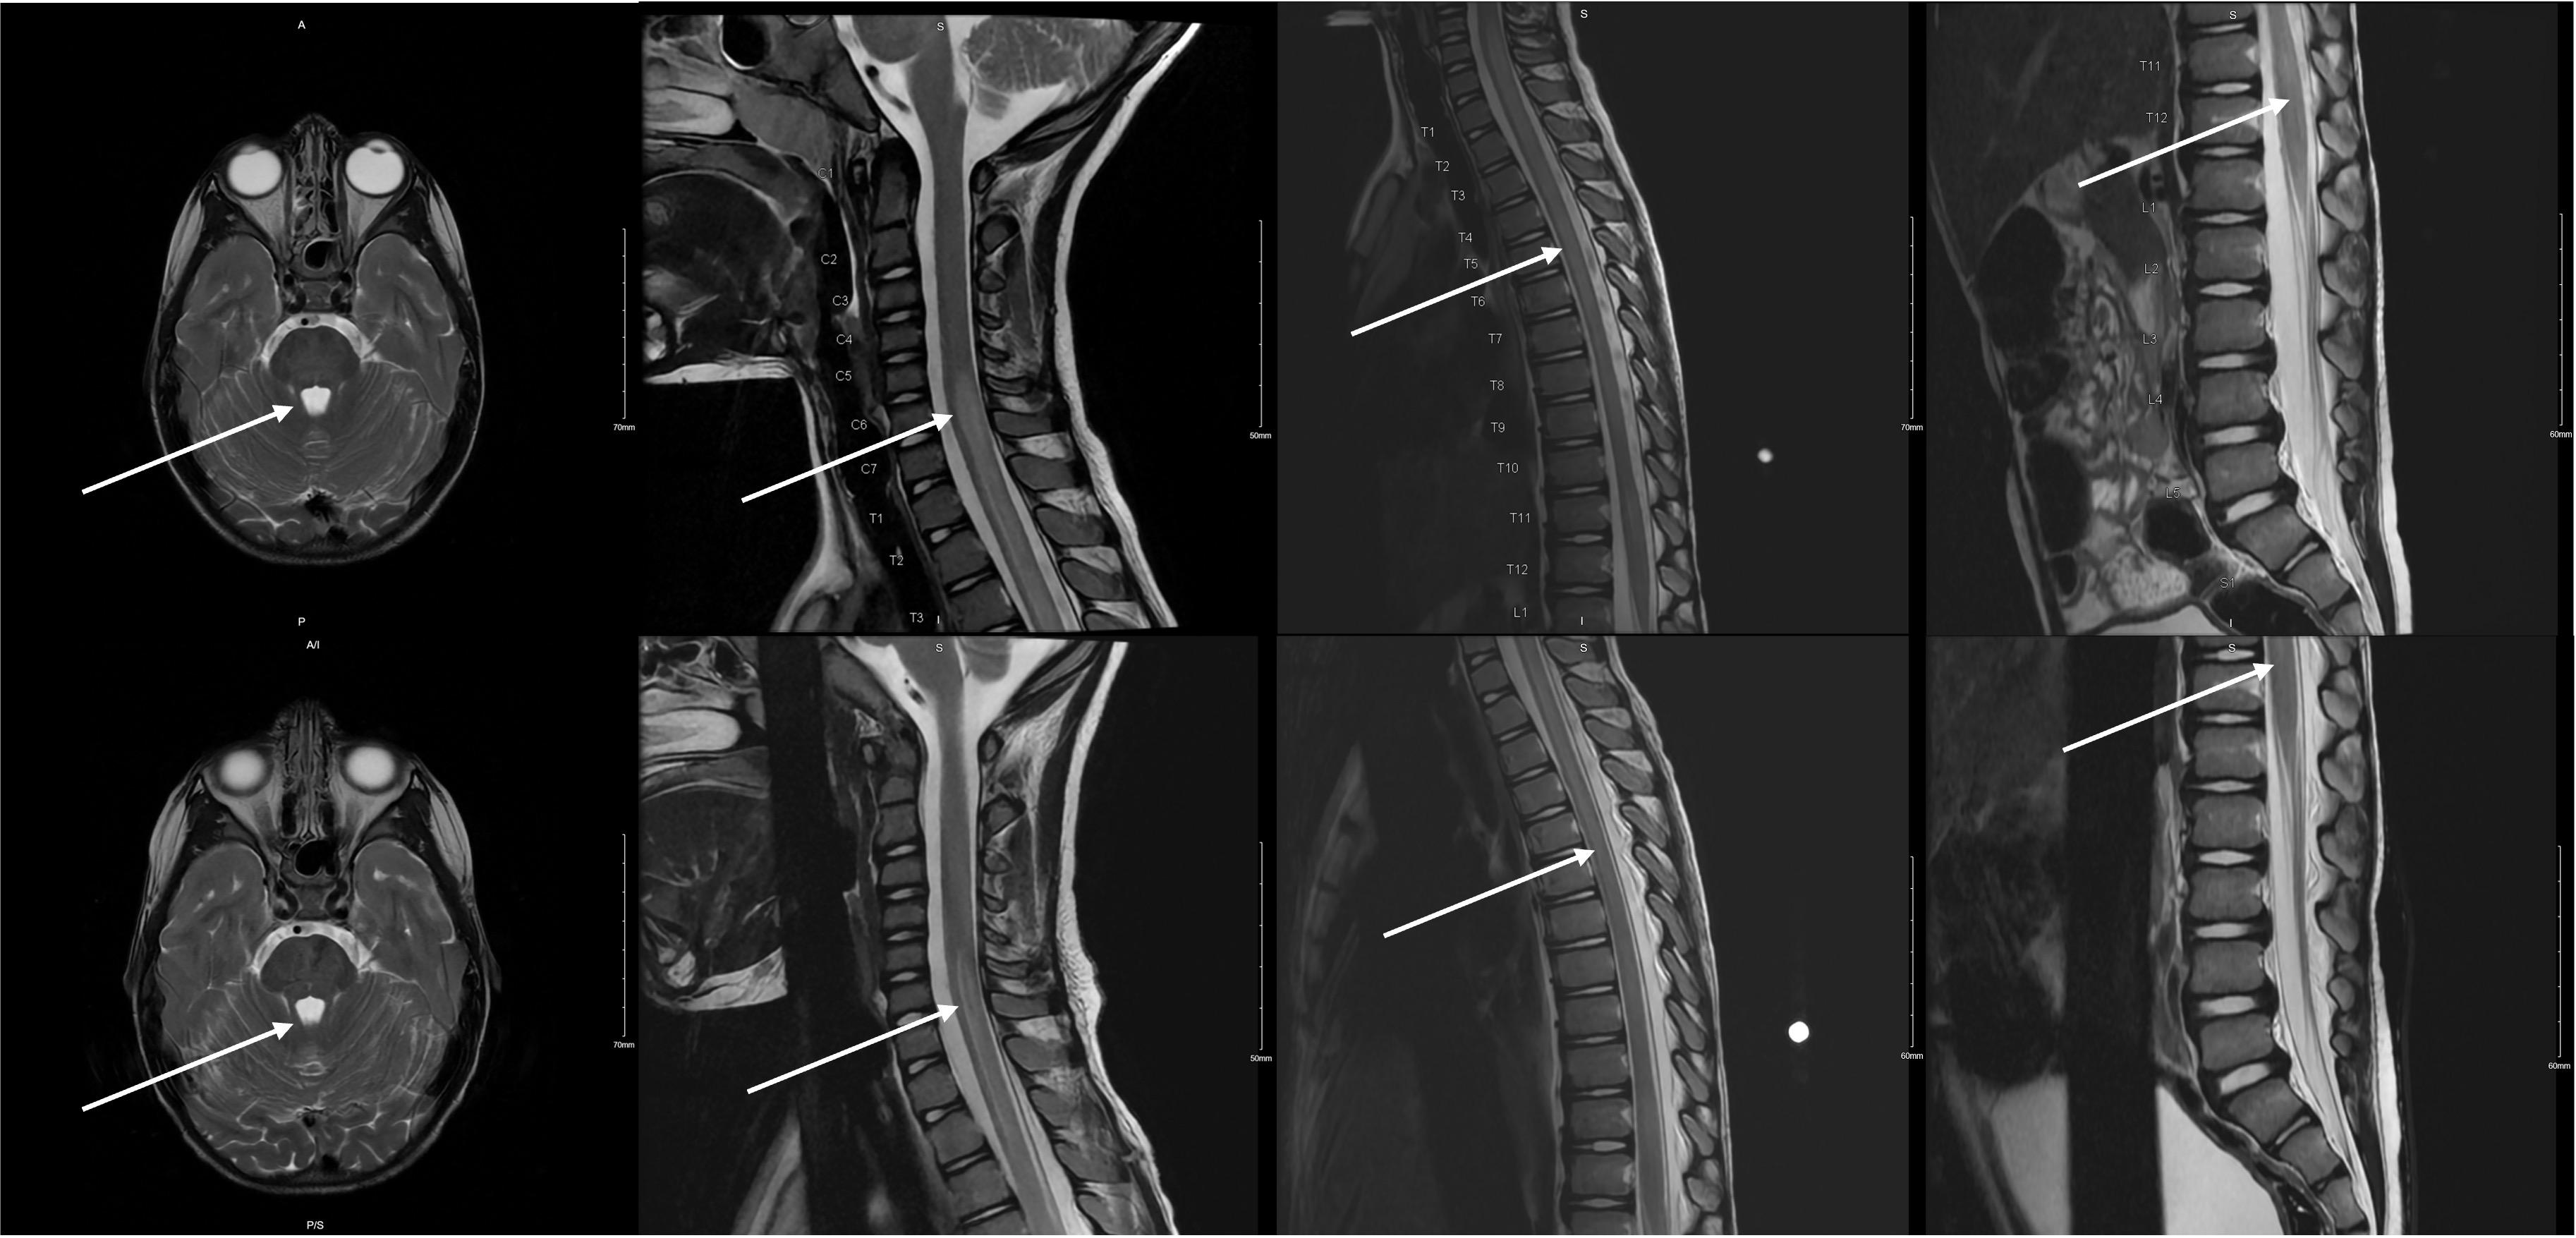

步态障碍在儿科患者可以与广泛的感染性,创伤性,肌肉骨骼和神经学的病因诊断陷阱。此外,孩子们可能很难表达他们的痛苦,也很难检查。这个病例强调了慢下来获取详细病史以及对我们的儿科患者进行彻底检查的重要性,这在繁忙的急诊科可能是具有挑战性的。我们提出一个病例急性横断脊髓炎(ATM)在一个四岁的男性谁提出了一天的跛行和双侧腿痛与负重。看护人报告说可能是日托所里的斗殴造成的远端创伤。神经学检查显示明显异常,包括双侧髌骨反射亢进、双侧下肢无力、阵挛和步态失调。脑和脊柱MRI显示纵向广泛的ATM伴脊髓水肿。尽管缺乏感染前驱症状的证据,但脑脊液感染分析显示肺炎支原体是病原体。静脉注射(IV)甲基强的松龙和阿奇霉素治疗导致出院后几周内所有神经系统后遗症的最终解决。本报告强调了在鉴别以步态疾患为表现的儿科患者时考虑ATM的重要性,以及彻底的神经学检查的重要性,否则诊断将被错过。主题:小儿急诊医学、小儿神经病学、急性横断面脊髓炎、小儿步态障碍。

Gait disturbances in pediatric patients can be wrought with diagnostic pitfalls given the broad infectious, traumatic, musculoskeletal, and neurological etiologies. Furthermore, children can have difficulty communicating their pain and can be hard to examine. This case highlights the importance of slowing down to obtain a detailed history as well as perform a thorough exam in our pediatric patients, which can be challenging in a busy emergency department. We present a case of acute transverse myelitis (ATM) in a four-year-old male who presented with a one-day history of limp and bilateral leg pain with weight bearing. The caretakers reported a possible remote trauma from roughhousing at daycare. Neurological examination revealed significant abnormalities including bilateral patellar hyperreflexia, bilateral lower extremity weakness, clonus, and gait ataxia. A brain and spinal MRI revealed longitudinally extensive ATM with cord edema. Despite the lack of any evidence of infectious prodrome, cerebrospinal infectious analysis revealed Mycoplasma pneumonia as the causative agent. Treatment with intravenous (IV) methylprednisolone and azithromycin therapy led to eventual resolution of all neurological sequelae within a few weeks of discharge. This report emphasizes the importance of considering ATM in the differential of pediatric patients presenting with gait complaints, as well as the importance of a thorough neurologic exam, without which the diagnosis would have been missed.